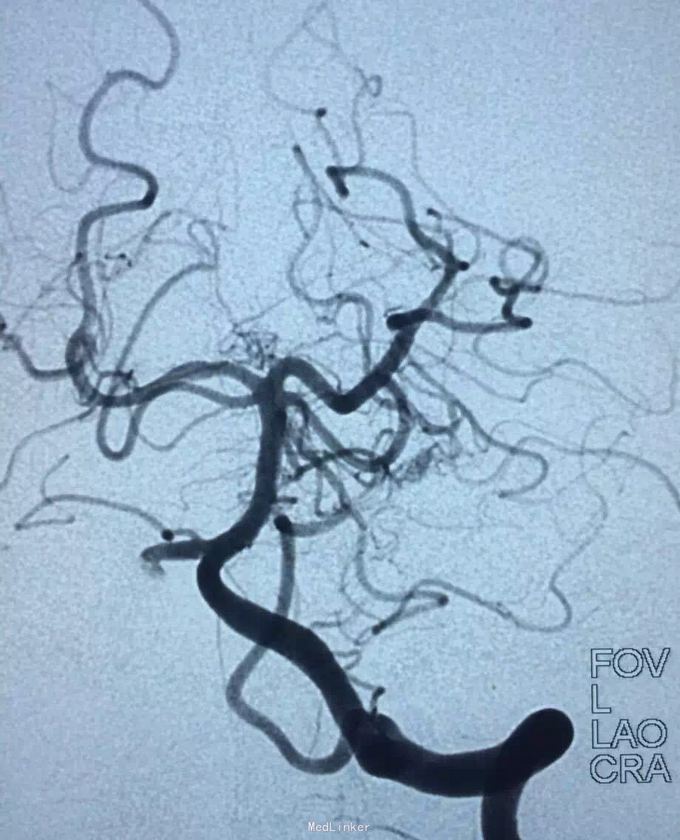

AVM

小脑出血

介入治疗

待随访